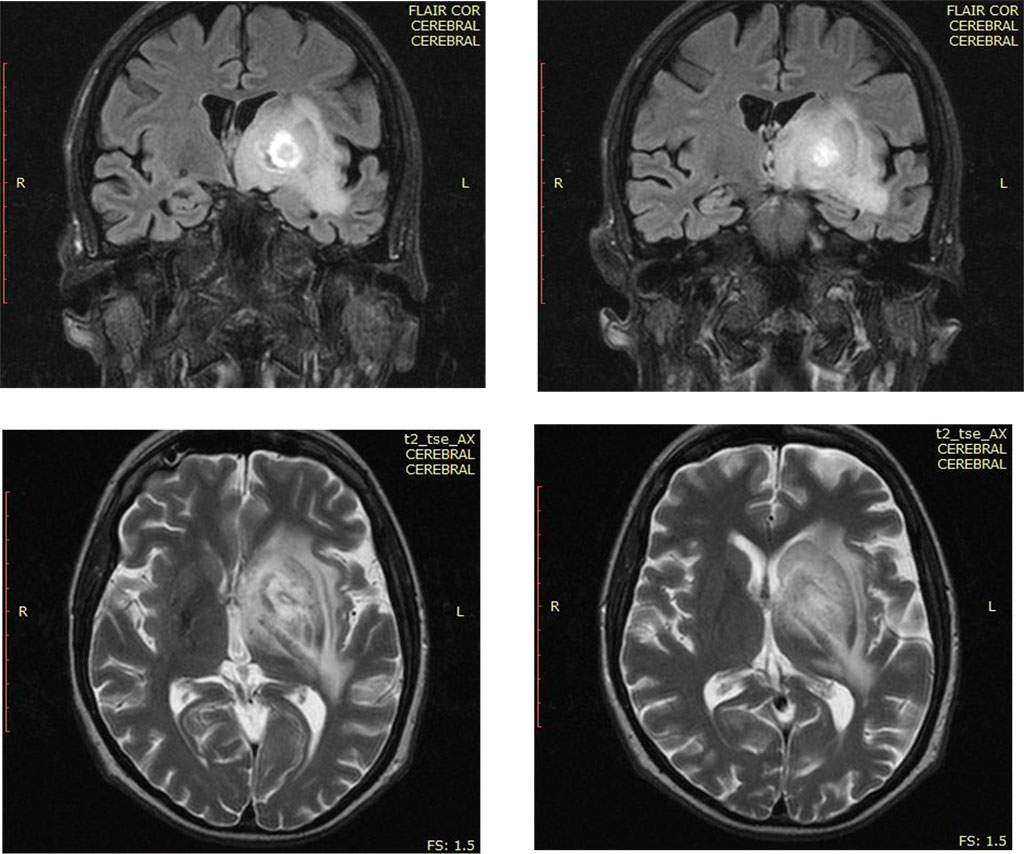

Because the state of the patient is worsening, and depression syndrome is progressive a cerebral computed tomography (CT) scan was performed and revealed a left fronto-parietal expansive brain process. A cerebral magnetic resonance imaging (MRI) with gadolinium contrast followed and showed a heavy solid mass in deep cerebrum area, in which gadolinium is captured peripherally. That mass was located fronto-parietal with extension to left basal nuclei (Fig. 1). A similar but smaller mass was discovered in left occipital area also.

Fig.1. The

appearance of the cerebral MRI of the cerebrum tumor processe

Source: Authors' own conception

The therapy for human immunodeficiency and toxoplasmosis was initiated (the MRI imaging was extremely suggestive and the serology for toxoplasmosis was positive), with favorable evolution, improving overall state and depression and reducing the size of the intracerebral mass.